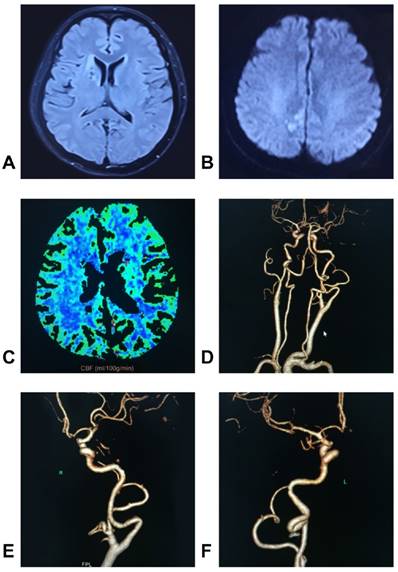

DICAs are not uncommon ICA diseases and can be classified by their tortuosity, coiling and kinking. Due to blood flow reduction, DICAs can result in symptoms of the brain and eyes due to insufficient blood supply. In addition, DICAs can be present with a pharyngeal bulge and pulsation. The diagnostic tools for DICAs include Doppler ultrasonography, CTA, MRA and DSA. Some DICAs, particularly those with symptomatic kinking, should be treated surgically, and the appropriate treatments for DICAs have their own surgical indications. Several methods, including correction of the bending of ICAs and shortening of ICAs, have been developed for the treatment of DICAs. The appropriate treatments for DICAs can result in good outcomes and are associated with low morbidity and mortality rates. However, despite the success of surgical reconstruction, an appropriate therapeutic treatment remains the subject of numerous debates due to the lack of multicentric, randomized and prospective studies. Here, we provide a typical case of DICA in which end-to-end anastomosis to shorten the ICA was performed. This case is shown in Figure 9.

Figure 9

Images of a typical case. A-B: MRI showed infarction of the right hemisphere, C: Perfusion MRI showed a reduction of cerebral blood flow in the right hemisphere, D-F: The CTA showed bilateral kinkings, and the right one was serious. G-H: The Doppler ultrasound showed that the proximal blood flow of the right ICA kinking was 48.7 cm/s, and the distal blood flow was 105.8 cm/s, I-J: The operation showed that the kinking was removed, and end-to-end anastomosis was performed to shorten the ICA. K-L: The intraoperative DSA showed that the ICA recovered its normal shape.